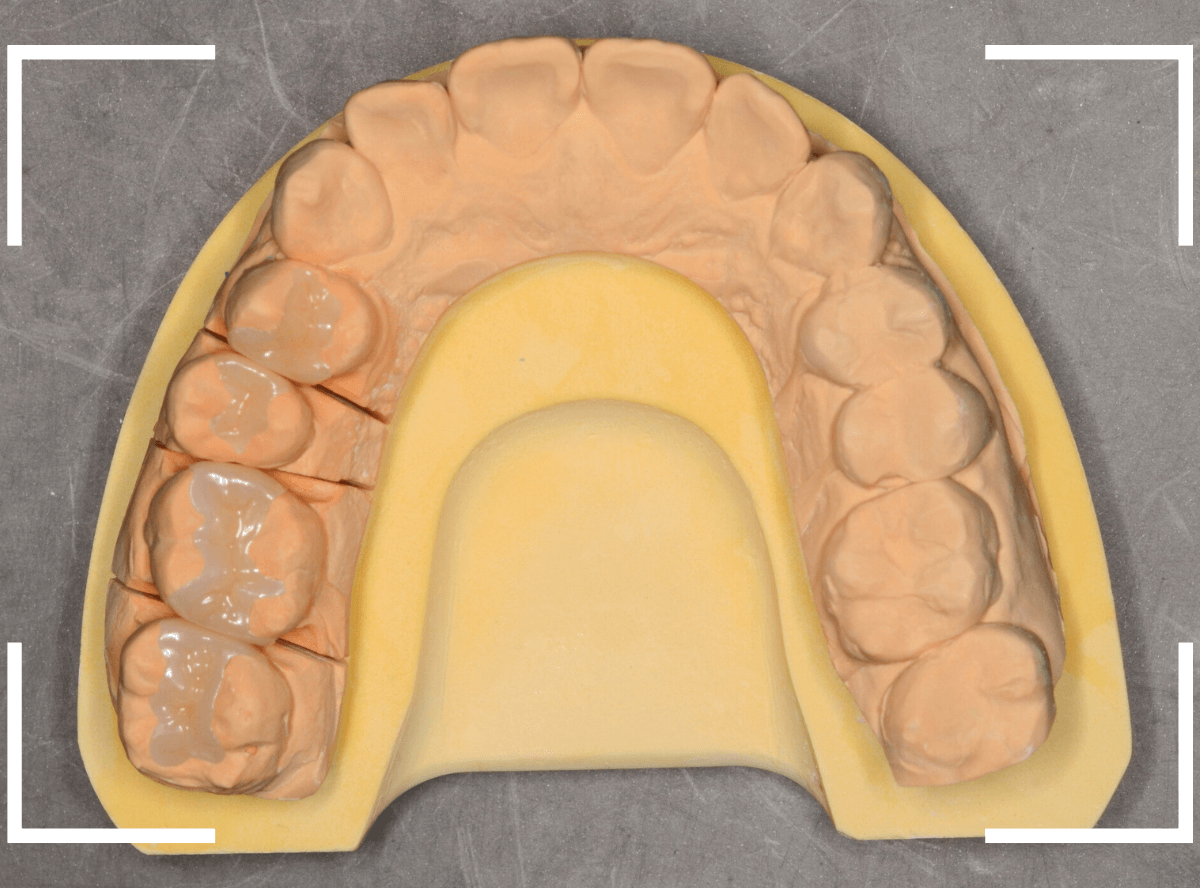

模型上で精密に製作します。

こちらが、型をとって製作した模型です。

分割模型といって、矢印の部分で模型を外せる仕様になっています。

細かい歯の形態を手元でしっかり確認して製作できるわけです。

暗く操作性の悪いお口の中での処置よりも、精密度は高くなりますよね。